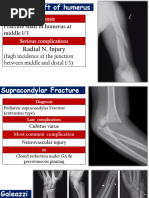

Pathologic Conditions

Fractures of Bones